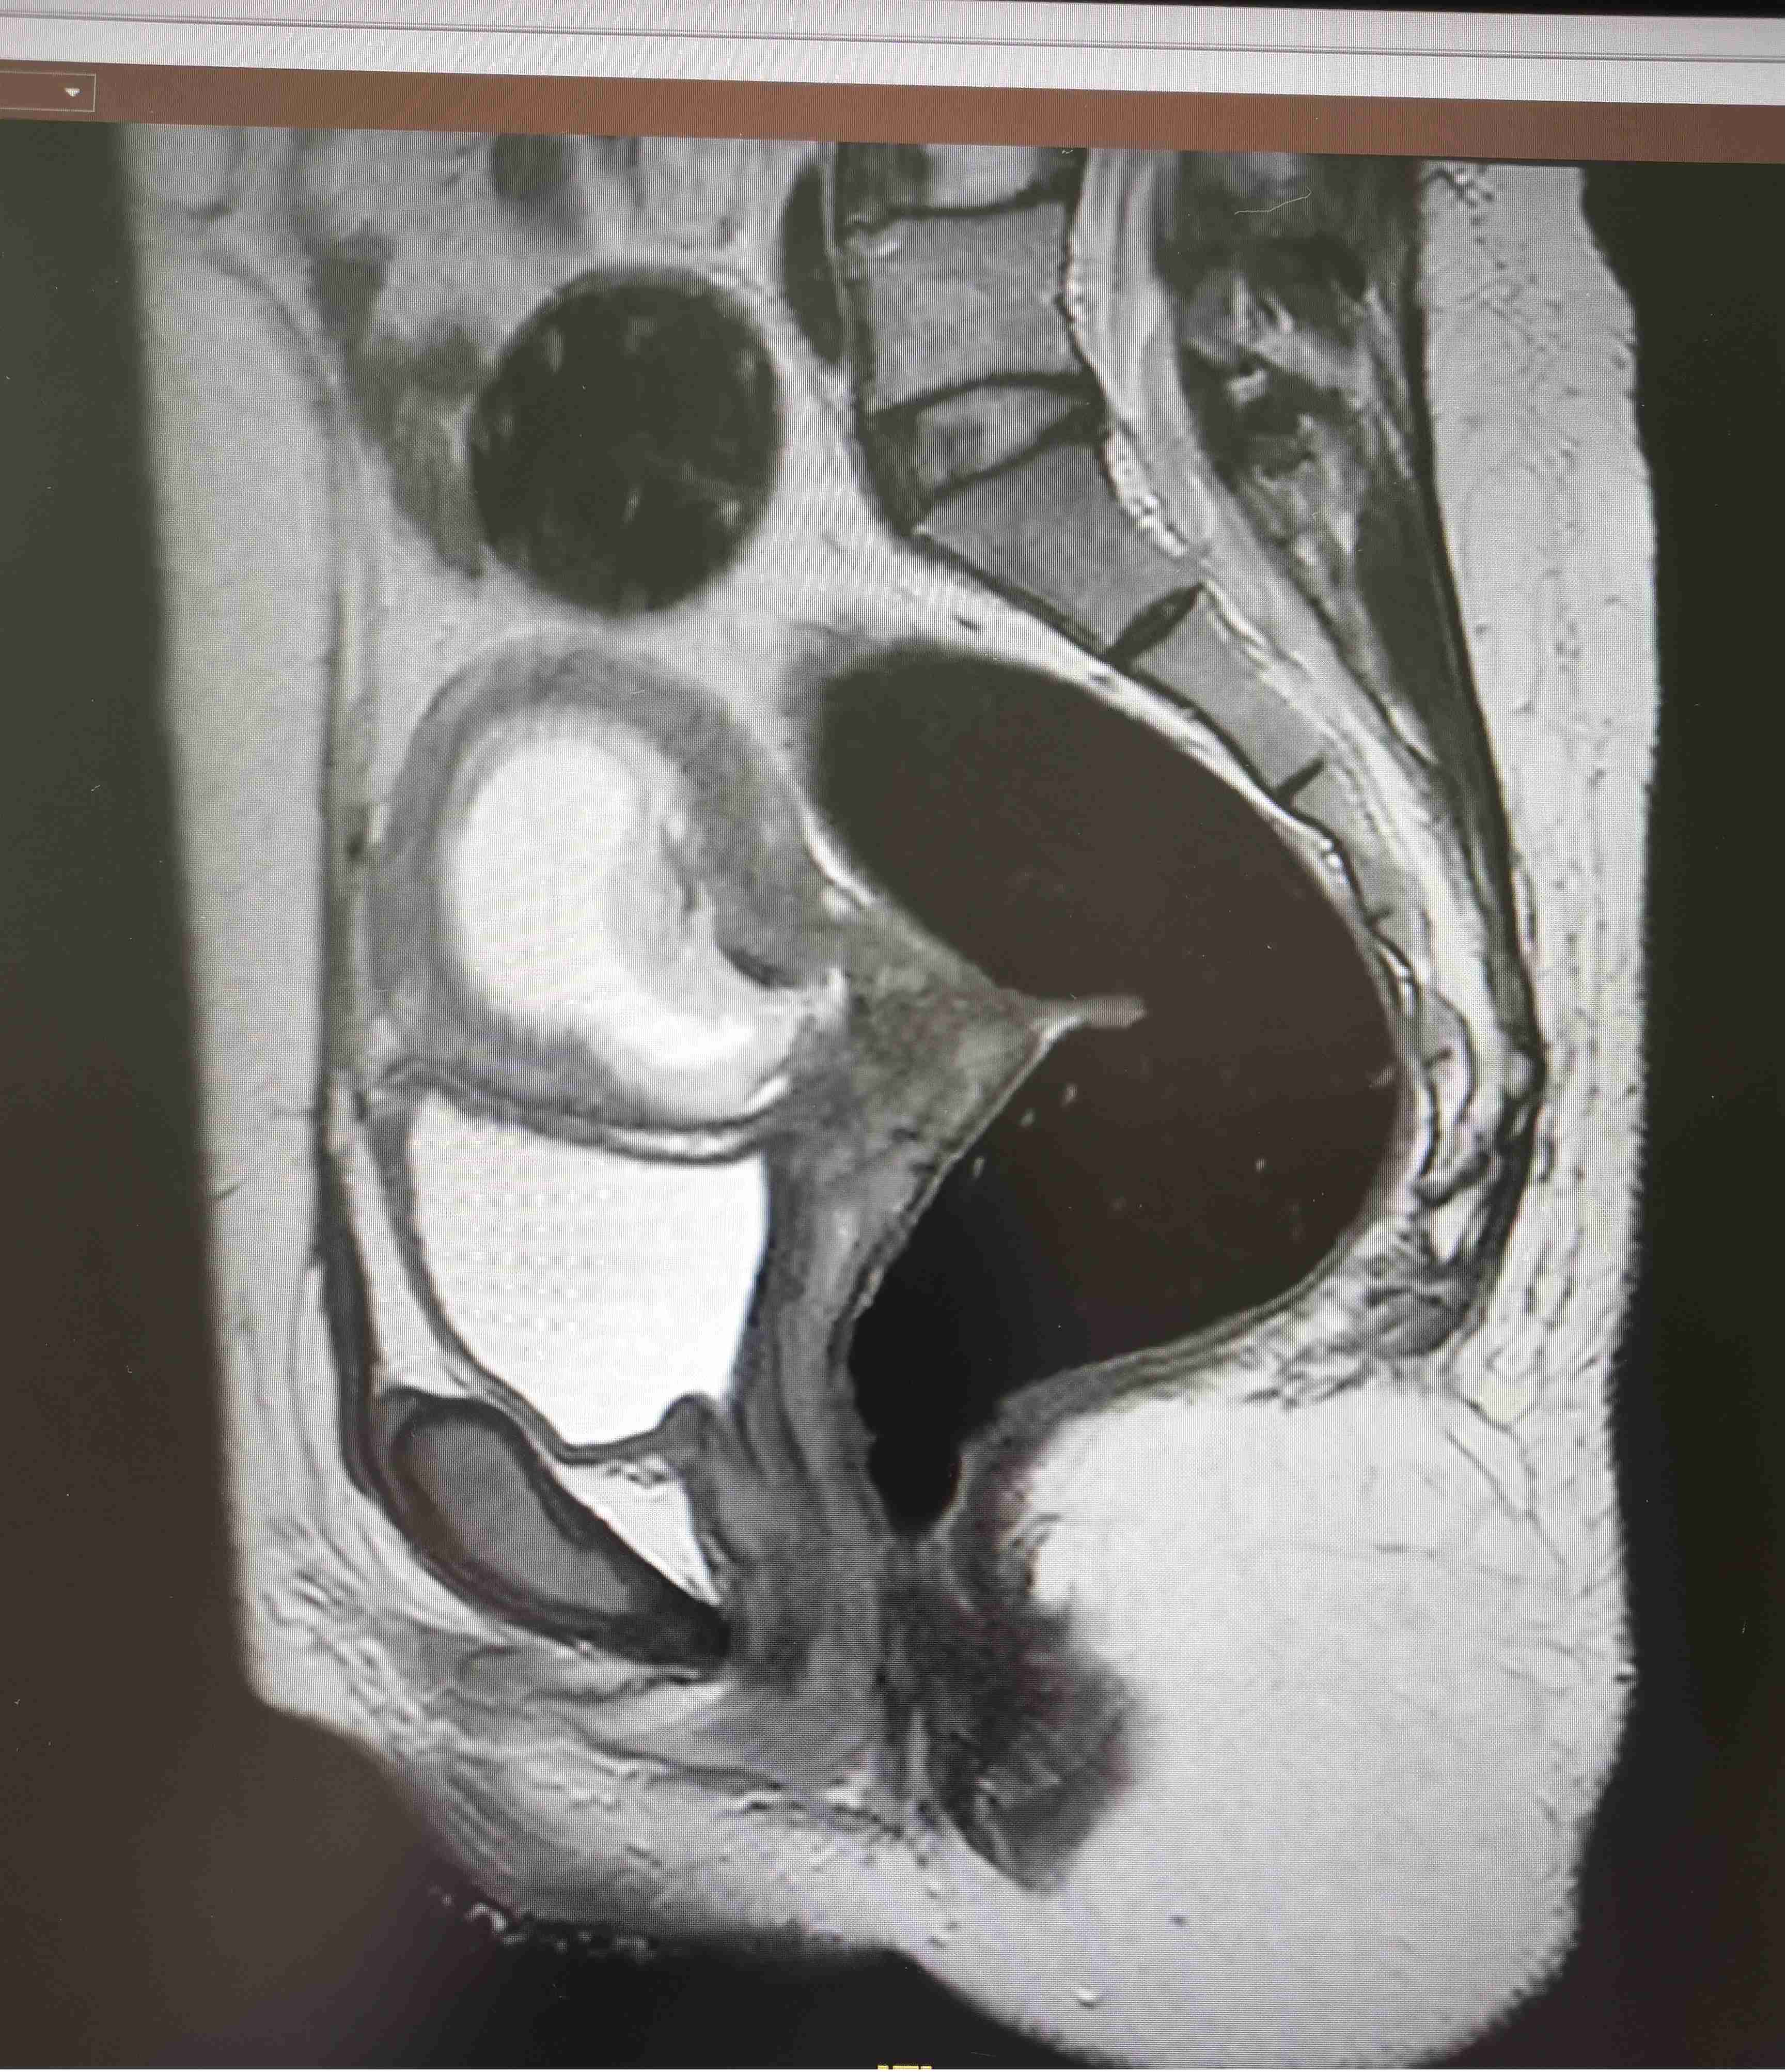

36岁的陈女士(化名)停经8周余,因胚胎位置异常就医检查,超声结果显示其孕囊恰好附着于子宫前壁剖宫产瘢痕处,且该区域肌层已完全缺失,仅靠一层薄如蝉翼的浆膜层包裹着存活胚胎,属于凶险程度极高的瘢痕妊娠。

“正常子宫肌层是支撑子宫的‘承重墙’,而陈女士瘢痕区仅剩的浆膜层毫无弹性和韧性,就像糊窗户的薄纸,稍受外力就可能破裂。”该院妇科主任医师刘爽介绍,“手术中器械轻微摩擦、牵拉,甚至剥离病灶时的微小张力,都可能引发子宫穿孔和致命性大出血,对手术精度和团队协作要求极高。”

为最大限度保障患者安全与生育需求,妇科团队制定个性化微创诊疗方案。手术当日,医护人员在腹腔镜实时监视下精准定位病灶,先通过负压平稳吸出妊娠组织,再对瘢痕缺损处进行精细化分层缝合修补,同时顺带处理了右侧输卵管系膜囊肿及腹腔粘连问题。整场手术耗时仅1小时余,全程出血量极少,进展十分顺利。